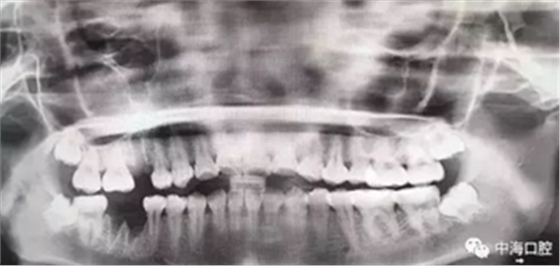

下面這兩張圖,據(jù)說拔牙費(fèi)時(shí)1.5小時(shí),收費(fèi)14000元。